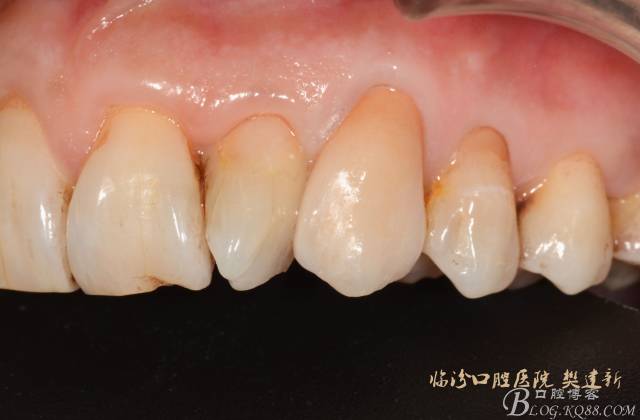

圖10 修復(fù)體代入口內(nèi)照

圖11

圖12 修復(fù)體代入口內(nèi)正面照